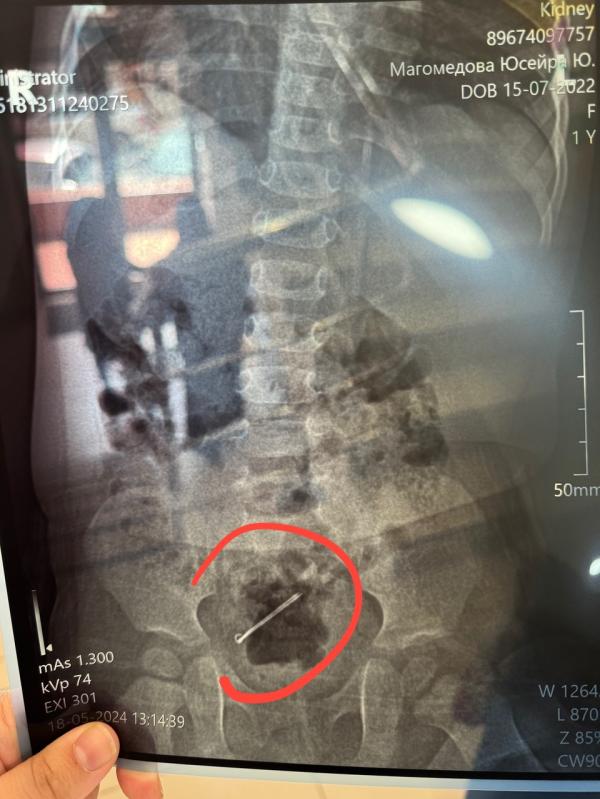

Девочки я только смогла зайти сюда . Мы были в кидней на рентгене, а потом у хирурга. Я эти дни вся перенервничала и сама не своя была, забывала даже что мне кто то может писать . Час назад Альхамдулиллях они вышли естественным образом. Я не могу вам передать мое облегчение и радость в этот момент . Столько человек делали дуа за мою малышку и Аллах ответил на дуа. Безграничная хвала Аллаху что все завершилось лучшим образом.